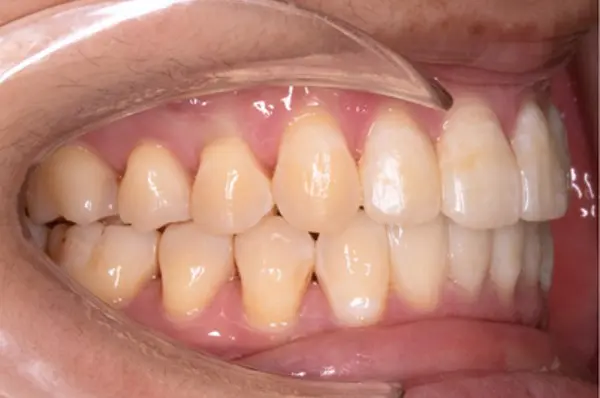

Crowding

Before